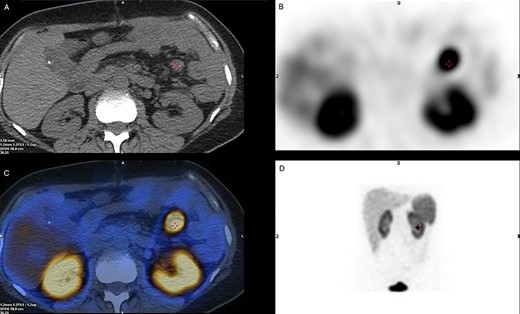

SPECT/CT Octreotide imaging. (A) A CT cross-section view indicating the location of the malignant lymph node. (B) A SPECT cross-section of the same plane indicating high uptake over the Region of Interest. (C) A combined view of SPECT/CT with superimposed images demonstrating hotspot over the malignant lymph node. (D) Octreotide SPECT coronal view showing the position of the malignant lymph node.

Initial basic laboratory investigations on presentation are mentioned above; however given the complexity of this case, further investigation was required. An octreotide single-photon emission computed tomography (SPECT/CT) imaging was performed in hope to identify any additional active tumour cells (Fig. 1). An avid ~15 mm node was noted in the proximal mesenteric jejunum (Fig. 2), as seen intra-operatively, with no additional pancreatic, small bowel or colonic uptake. Other specialized laboratory investigations included chromogranin A&B, which were within normal values of 20 and 88 pmol/L, respectively. 24-h urine 5-HIAA test was also normal of 14 μmol/24 h. The overall image and appearance closely points to a well-differentiated grade 2 neuro-endocrine carcinoma.